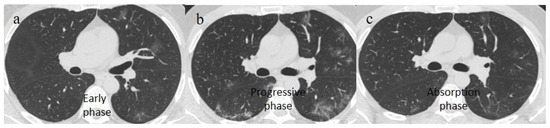

| Typical Appearance | GGOs with a crazy-paving pattern and consolidations in a peripheral and posterior or central-peripheral distribution; multilobar involvement; vascular enlargement, the halo and reversed halo sign; subpleural and parenchymal bands; and architectural distortion. They were predominant since the Delta wave. |

| Typical findings of interstitial pneumonia with peripheral or peripheral central distribution from the wild/type variant since Delta variant |

| Absence of pneumonia or atypical findings during the Omicron wave | |||